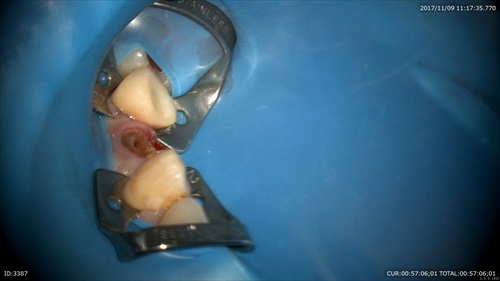

ラバーダムをかけて

根管てこんなに汚れているのです。

ここにもう1つ根管がある気が。

やはり!!